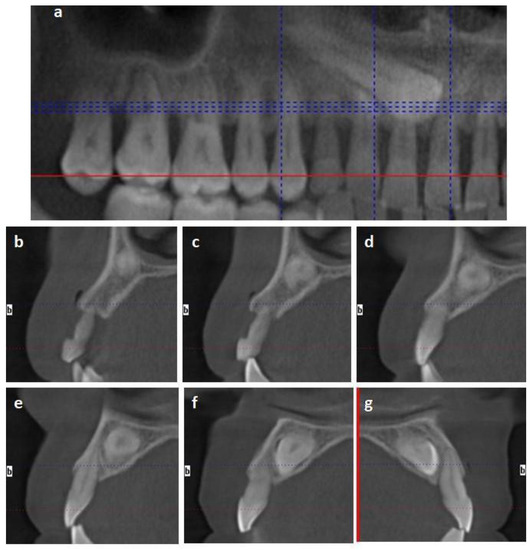

2.1.2. Case 2

2.2.2. Case 2